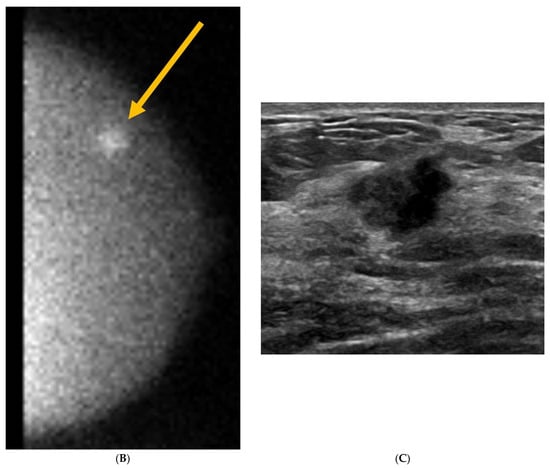

9. Molecular Breast Imaging (MBI)